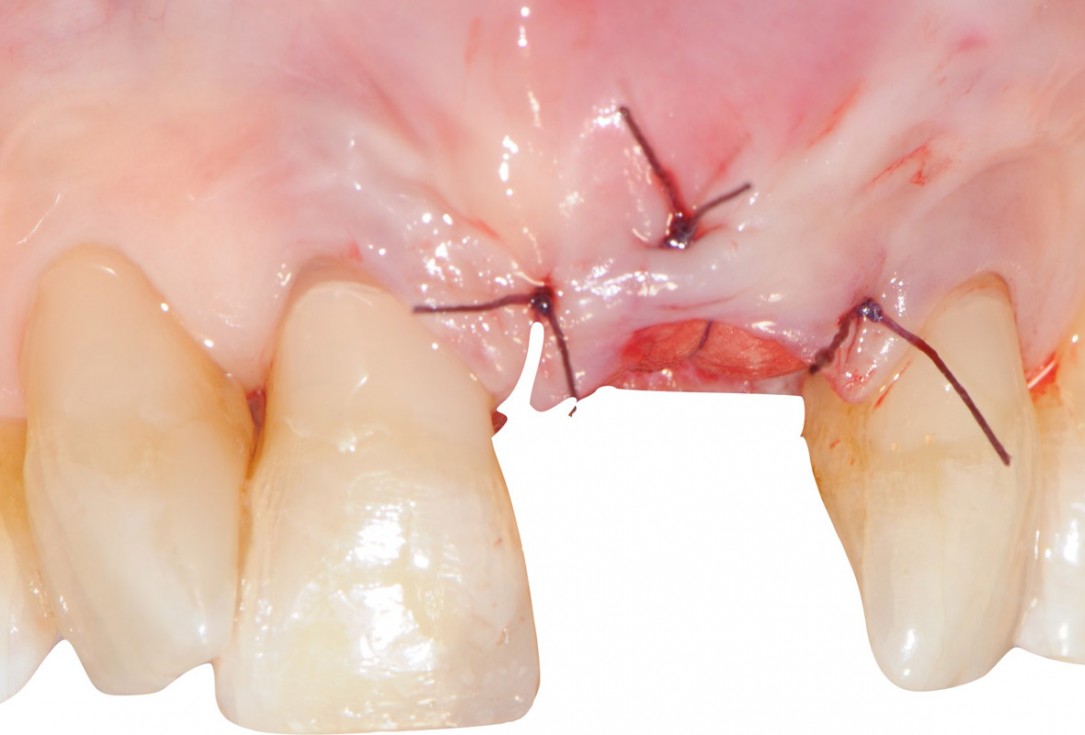

11/18 - Stabilization of the mucosal flap by nylon sutures 5/0Tooth extraction and socket sealing with mucoderm® - Dr. A. Rossi

12/18 - Occlusal view of the wound closureTooth extraction and socket sealing with mucoderm® - Dr. A. Rossi